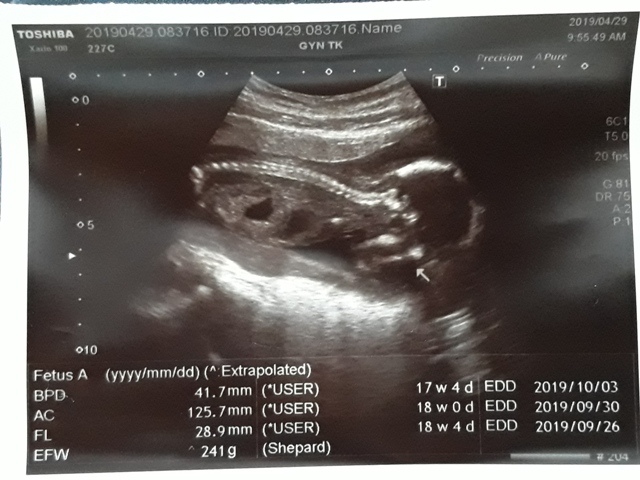

| 仙人掌(2019/04/29)的真心話 星期一 天氣晴 編號19-110 |

近三次產檢資料統計

| 日期/項目 | BPD | AC | FL | EFW | 心跳 |

| 2019年03月04日 | 無資料 | 無資料 | 無資料 | 無資料 | 無資料 |

| 2019年04月01日 | 28.9mm | 77.9mm | 14.2mm | 107g | 153 |

| 2019年04月29日 | 41.7mm(44%) | 125.7mm(61%) | 28.9mm(103%) | 241g(125%) | 150 |

| BPD:胎兒頭骨橫徑 AC:胎兒腹圍的長度 FL:胎兒大腿骨的長度 EFW:胎兒的體重 | |||||